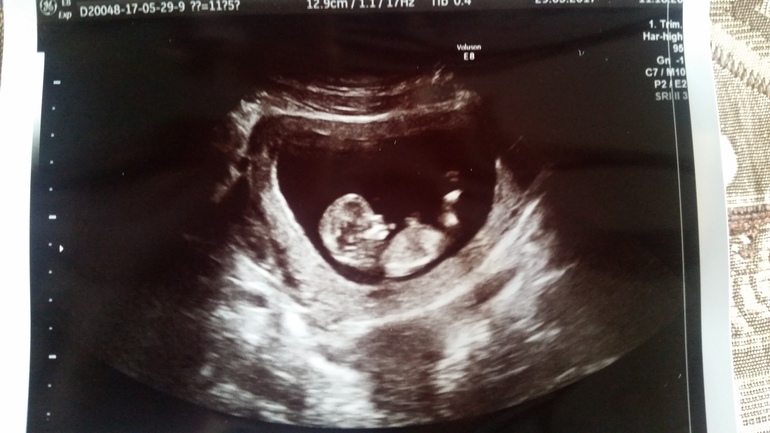

1 скрининг

Пошла платно, к своему любимому акушеру - темпераментному греку.

11 недель 5 дней. На экране картофелинка-креветочка) Развитие четко на этот срок, все измерения ок, тока плацента низковата. "Жесткий и глубокий секс не рекомендую " - сказал врач, подмигнув Пашке. На что я хмыкнула и говорю, о каком сексе вообще речь, я к вечеру превращаюсь в труп рядом с тазиком. Врача это не смутило: "Ну поблевала и вперед, на полшишечки"))) И у этого человека я опять собираюсь рожать..

По половому бугорку сказал, что 70% опять пацан будет. Блин (( Ну ладно, в этом много плюсов, хотя, конечно, хотелось розово-желтых бодиков докупить...и бантики-цветочки. Эх. Ну бог с ним, главное здоровенький.

Ну и первое фото карапуза: